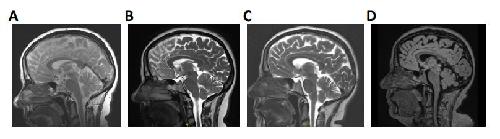

A novel KCNC3 gene variant in the voltage-dependent Kv3.3 channel in an atypical form of SCA13 with dominant central vertigo.,

Bernhard FP,Schütte S,Heidenblut M,Oehme M,Rinné S,Decher N,

Front Cell Neurosci. October 2, 2024; 18:1662-5102.